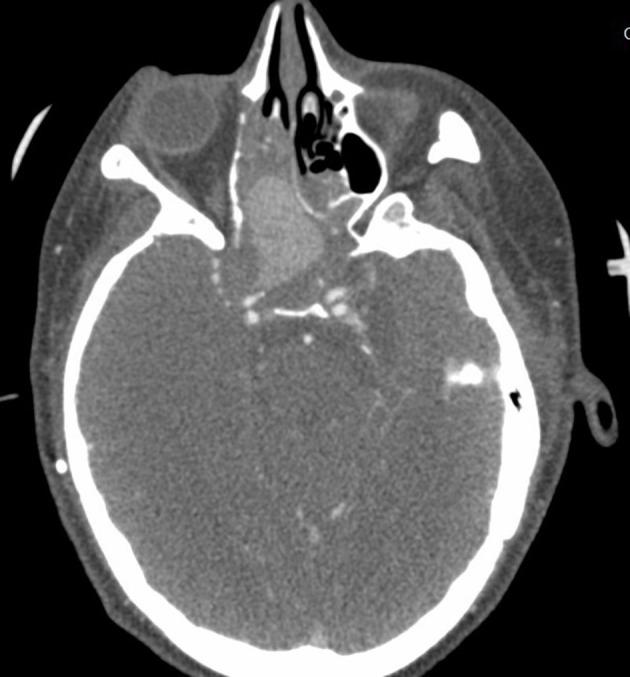

A 24-year-old female with history of traumatic brain injury with associated skull fractures due to a gunshot wound to the head 6 months prior presented to the ED in hemorrhagic shock secondary to epistaxis. After stabilization with the administration of blood products, Computed Tomography with Angiography (CTA) imaging of the head and neck was obtained and revealed a 3.1 × 2.2 × 2.5 cm pseudoaneurysm of the cavernous portion of the right internal carotid artery penetrating through the base of the skull into the ethmoidal sinus. The patient was taken for formal angiography by interventional radiology-and a partially thrombosed daughter sac of the initial aneurysm was identified and believed to be the source of the hemorrhage. The aneurysm was successfully coiled and occluded using ONYX embolization. Postoperatively, the patient returned to her baseline mental status without any acute complaints. The patient was discharged back to her nursing home 2 days later with a 3-week follow-up CTA revealing persistent occlusion of the aneurysm and a patent internal carotid artery.

一名24岁女性,6个月前因头部枪伤导致创伤性脑损伤并伴有颅骨骨折,因鼻出血继发失血性休克被送往急诊科。在输注血液制品使其病情稳定后,对头颈部进行了计算机断层血管造影(CTA)成像检查,结果显示右侧颈内动脉海绵窦段有一个3.1×2.2×2.5厘米的假性动脉瘤,该动脉瘤穿过颅底进入筛窦。患者被介入放射科送去进行正式血管造影,发现了最初动脉瘤的一个部分血栓形成的子囊,并认为这是出血源。使用Onyx栓塞剂成功地对动脉瘤进行了弹簧圈栓塞和封堵。术后,患者恢复到基线精神状态,无任何急性不适主诉。患者于两天后出院回到养老院,3周后的CTA随访显示动脉瘤持续闭塞,颈内动脉通畅。